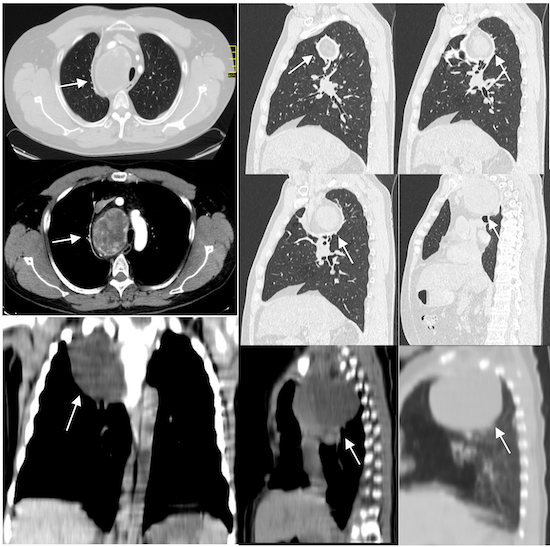

El ultrasonido tiroideo mostró una glándula agrandada con nódulos mal definidos bilateralmente. La tomografía computarizada cervicotoracica, después de la administración de medio de contraste, mostró un aumento de volumen el lóbulo tiroideo derecho, así mismo una masa realzada en el lado derecho del mediastino anterosuperior, por delante de los grandes vasos, que desplazan hacia delante la tráquea y el esófago y se extendía hasta el nivel de la bifurcación de la tráquea que mide aproximadamente 8.2 × 6.4 × 4.2 cms, (Figura2).

Figura 2. Tomografía computarizada cervicotoracicacon contraste muestra una masa realzada no heterogénea en el lado derecho del mediastino corte axiales, sagital y coronal.Localizacióndel bocio intratorácicoendotorácico primario (flechas blancas).